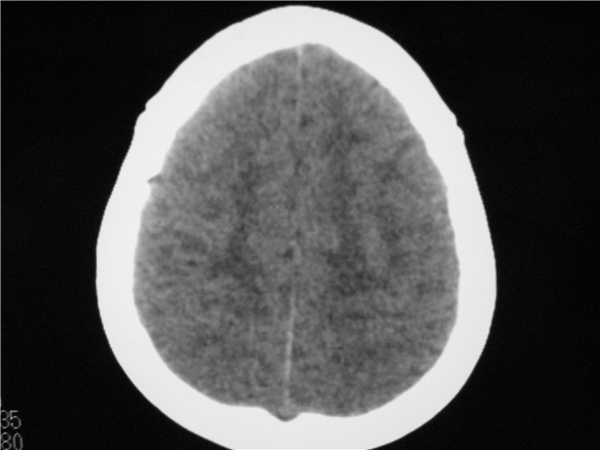

以下是引用随光逐影在2009-8-1 14:17:00的发言:[br]透明隔囊肿与vergae腔并存。

以下是引用zjzjr在2009-8-1 14:51:00的发言:[br]五、六脑室形成。